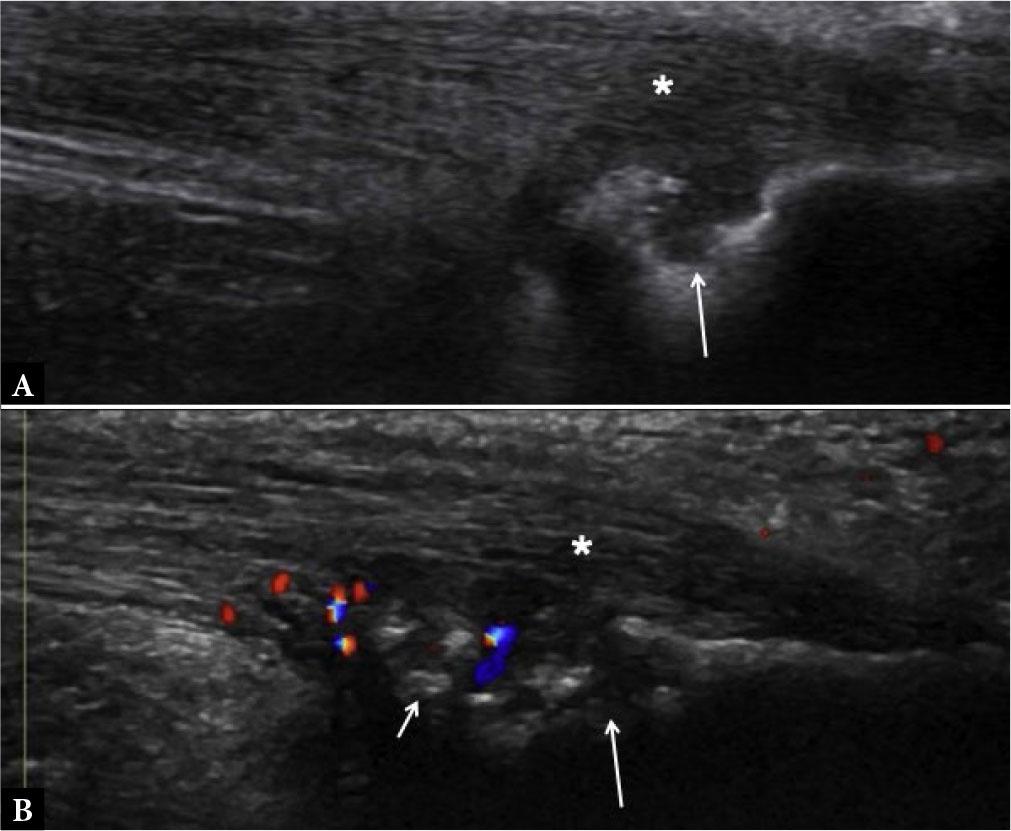

Fig. 16.

Enthesitis. Short-axis grayscale (A) and power Doppler (B) US images of tibialis posterior tendon (asterisks) show intra-tendinous and peritendinous thickening and power Doppler signal